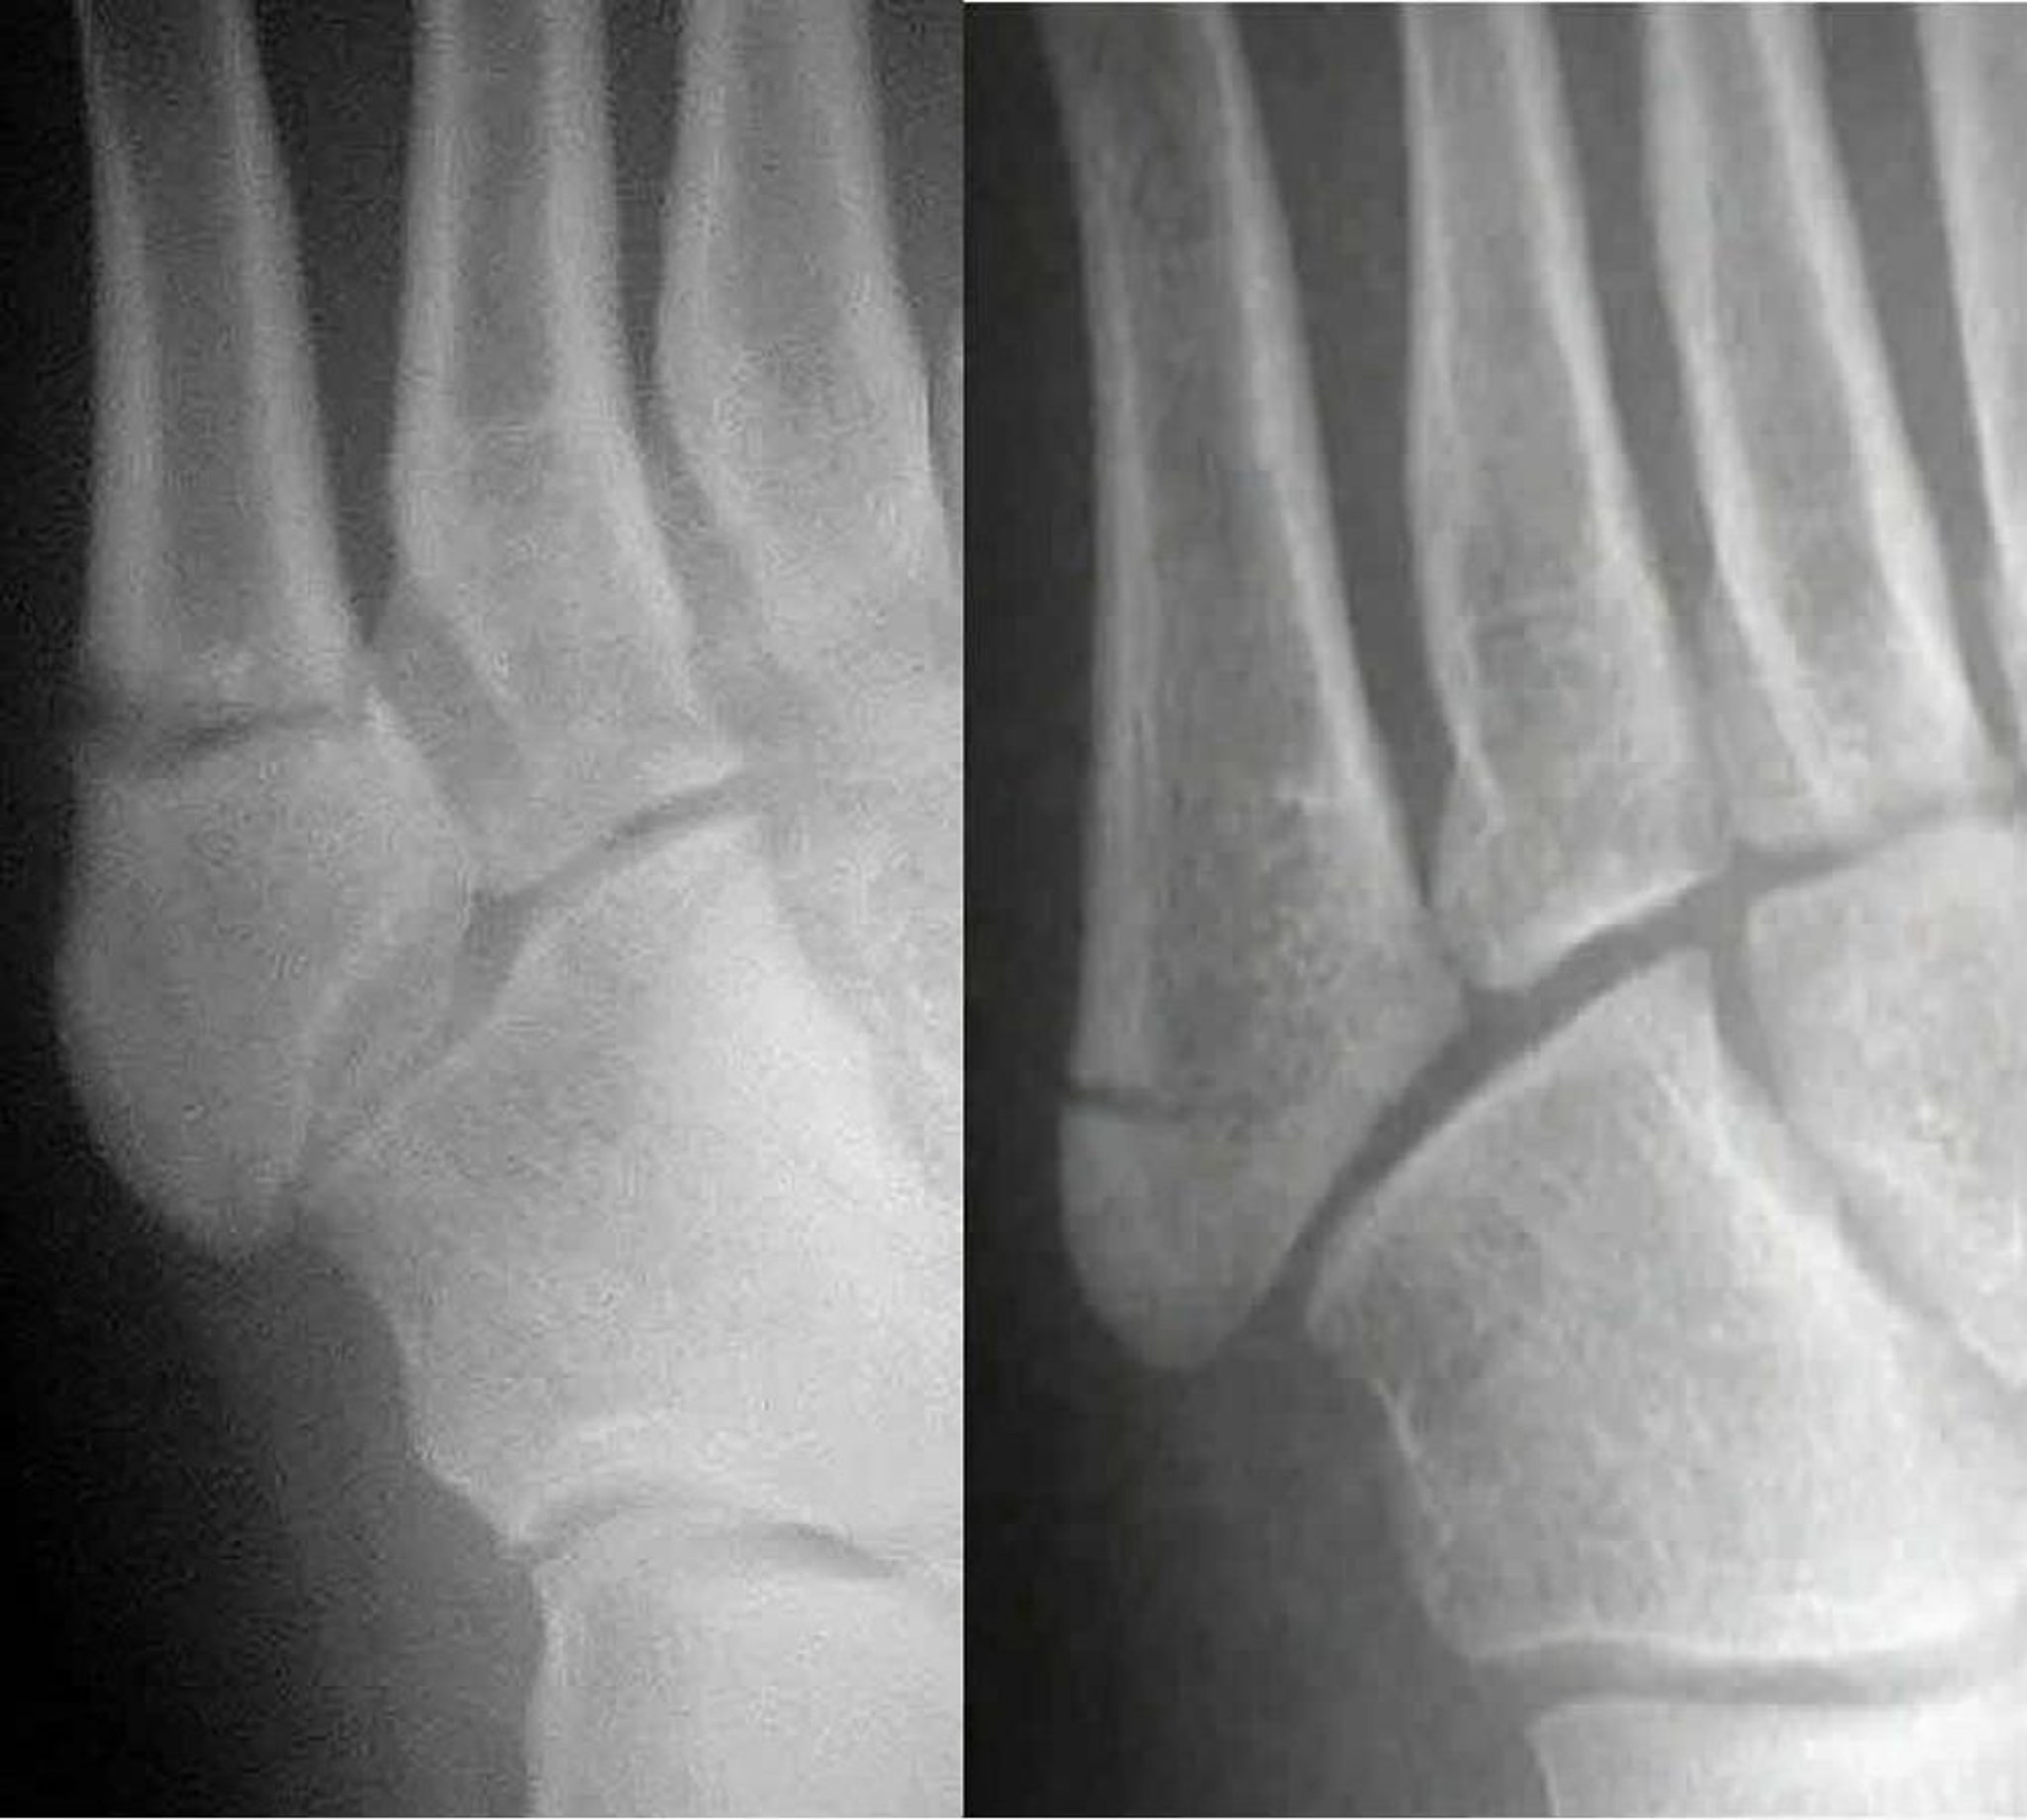

Fractures de Jones versus pseudo-Jones

Une fracture de Jones (à gauche) implique le 5e métatarsien; une fracture pseudo-Jones (à droite) implique la base du 5e métatarsien. Distinguer les deux est important car elles sont traitées différemment.